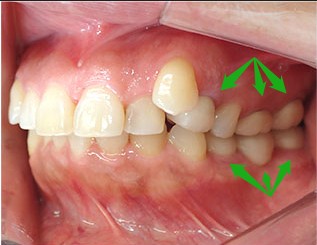

- ブリッジ 症例写真 B-0112FZC3本 女性モニターの方です。

この方は奥歯が虫歯で根だけになってしまっていました。 この歯は抜歯し、ブリッジで治しました。 当院では強度が高く色がきれいなジルコニアブリッジで治しております。 歯型を取らずに、口腔内スキャナーでジルコニアブリッジを作成しますので、精度の高いブリッジを入れることが可能です。 治療回数は3回でした。